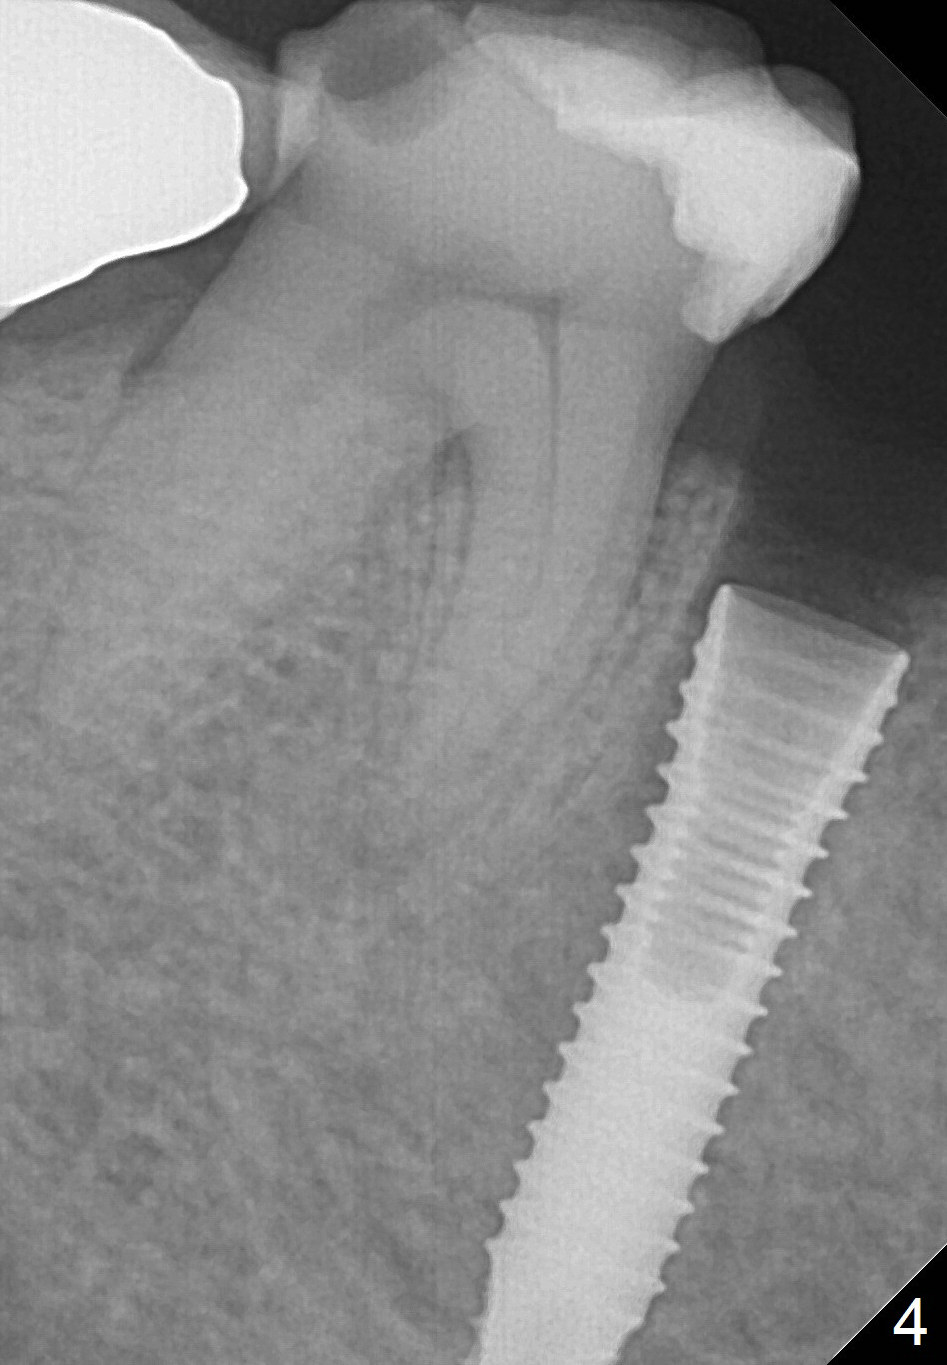

A 67-year-old woman fractures the tooth #29 three months post RCT. There is persistent periapical radio-lucency (Fig.1 yellow dashed line), which is close to the Mental Loop (red dashed line). Since the root of the affected tooth deviates distal, osteotomy will be established mesial (Fig.2). In fact it is not so easily accomplished; the osteotomy is initiated as mesial as possible (Fig.3 (yellow dashed line: original socket)). When a 3.8x16 mm implant is being placed, it is distal (Fig.4). The MO composite of the tooth #30 has to be trimmed for fabrication of an immediate provisional (Fig.5 <).

To reduce the chance to injury the buccally located loop, the osteotomy should be as lingual as possible. Initial depth is 19 mm (gingival level, Fig.3). In fact all of the three intraop PAs (Fig.3-5) do not show the Mental Loop until panoramic X-ray is taken immediately postop (Fig.6). There is no postop paresthesia. There appears no gap around the implant 3.5 months postop (Fig.7 >).